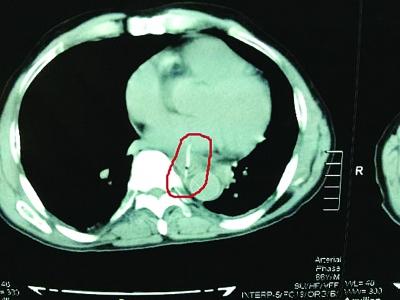

心脏中的鱼刺。

复查胸部CT,发现鱼刺前段经心包和左心房后壁,已深深刺入心脏,进入左心房约1厘米。由于已经形成血栓,栓子脱落,造成患者突发脑梗塞。